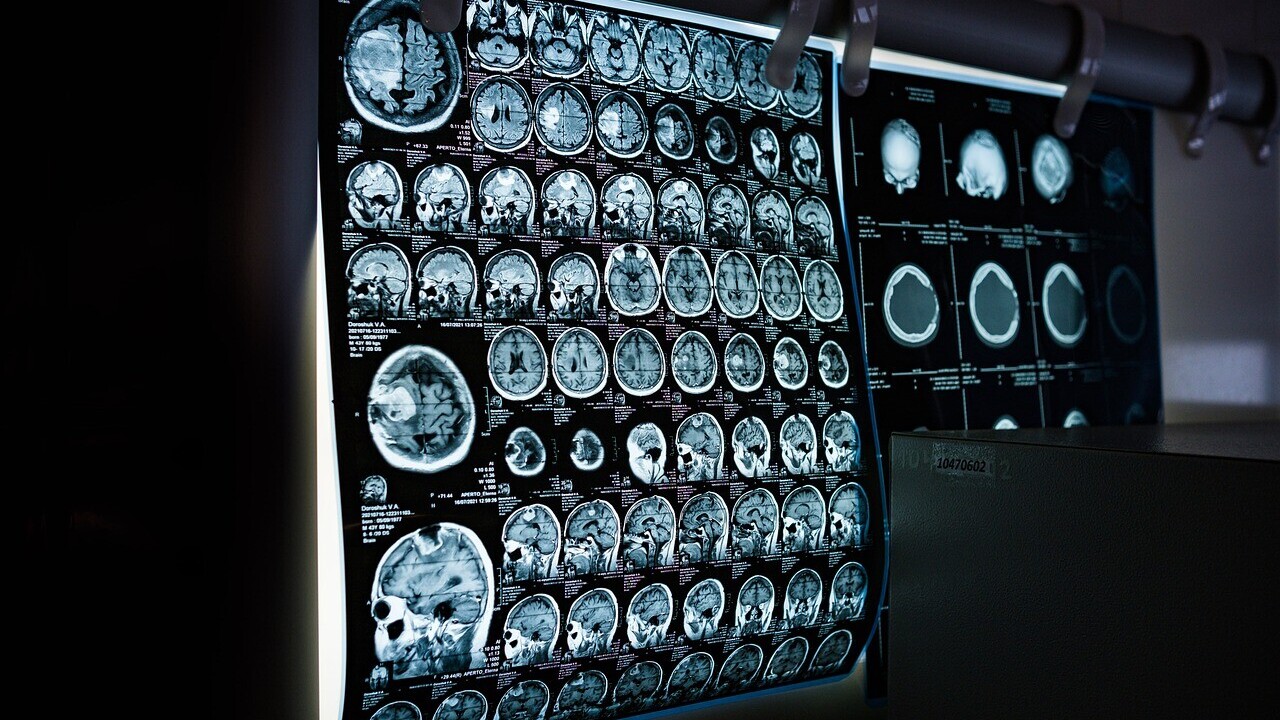

To develop and train an AI algorithm, the researchers used CT scans of 170 patients suffering from the two most common types of retroperitoneal sarcoma: leiomyosarcoma and liposarcoma. Then, they tested the algorithm on a set of 89 patients across Europe and the US.

The technology accurately assessed the aggressiveness of the tumours 82% of the time, while biopsies were correct in only 44% of the cases. The AI model was also able to predict the type of 84% of the sarcomas tested, compared to radiologists who could diagnose 65% of the cases.